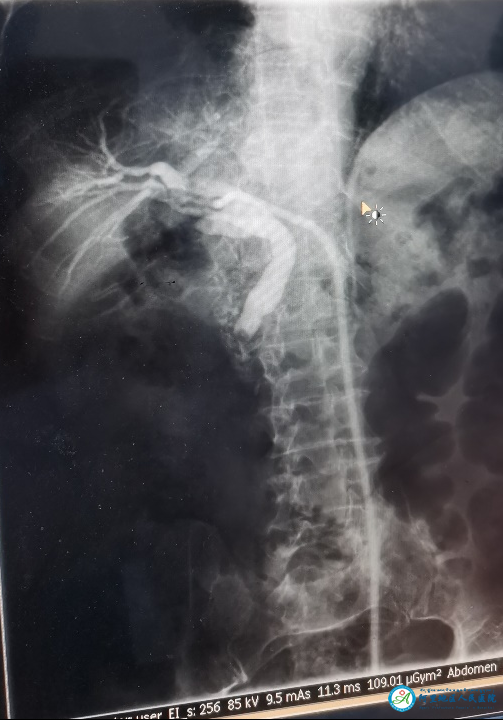

10月23日,阿里地區(qū)人民醫(yī)院急診科收治了一名急性胸痛患者,經(jīng)胸痛中心羅永百教授會診,高度懷疑主動脈夾層。這是一種極度兇險的疾病,確診需要進行主動脈的增強掃描。放射科援藏醫(yī)生劉正華在和羅教授溝通后,克服高壓注射器不能配套使用的難題,采用手動推注造影劑,完成了放射科第一例主動脈夾層的CT增強掃描,實現(xiàn)了阿里高原上CT增強掃描“零”的突破。